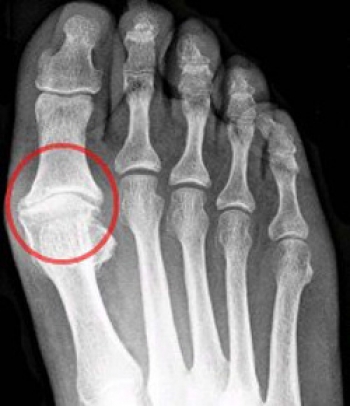

Ayak Başparmağında Çıkıntı

Ayak başparmağınızın başladığı yerde (tarak kemiği ile parmağın başlağı eklemde) şişlik, çıkıntı varsa halluks valgusunuz var demektir. Kadınların neredeyse % 40 ında bu yakınma vardır. Bu hastalıkta %70 oranında genetik bir eğilim vardır. Genetik olarak 1.-2. tarak kemikleri arasındaki açı fazla olduğunda zamanla başparmak diğer parmaklara yaklaşır ve bu keskin açılanma bir çıkıntı olarak görülür. Genetik eğilimliler dışında uzun yıllar topuklu, sivri burunlu ayakkabı giyenlerde de meydana gelebilir. Bu nedenle bu rahatsızlığı olan her 10 hastadan 9 u kadındır.